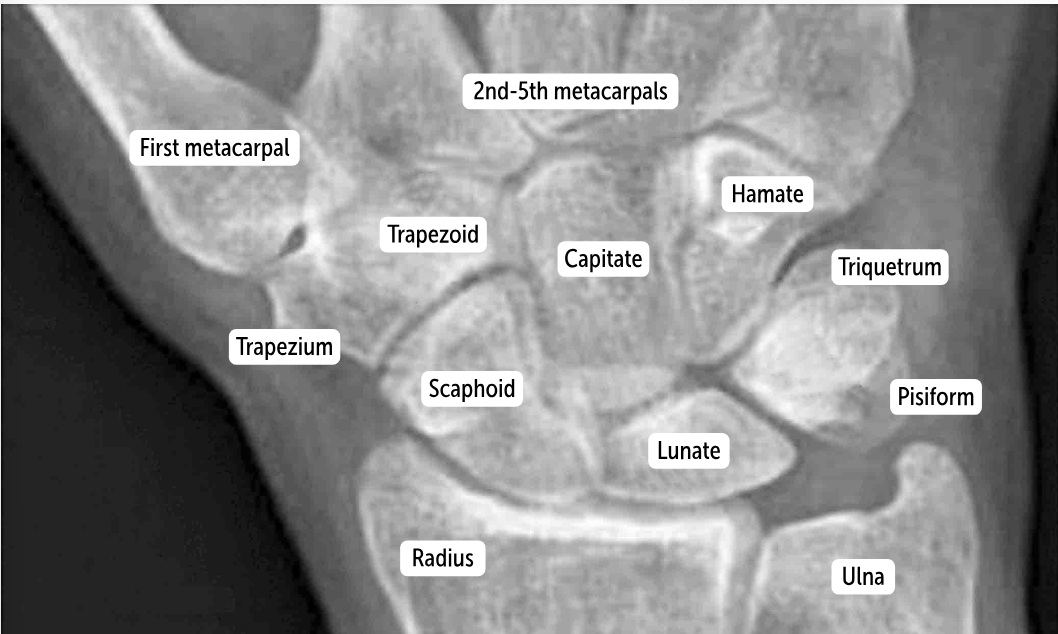

Carpal bones by row:

So Long To Pinky, Here Comes The Thumb

Scaphoid, Lunate, Triquetrum, Pisiform, Hamate, Capitate, Trapezoid, Trapezium

Scaphoid

Lunate

Triquetrum

Pisiform

Hamate

Capitate

Trapezoid

Trapezium